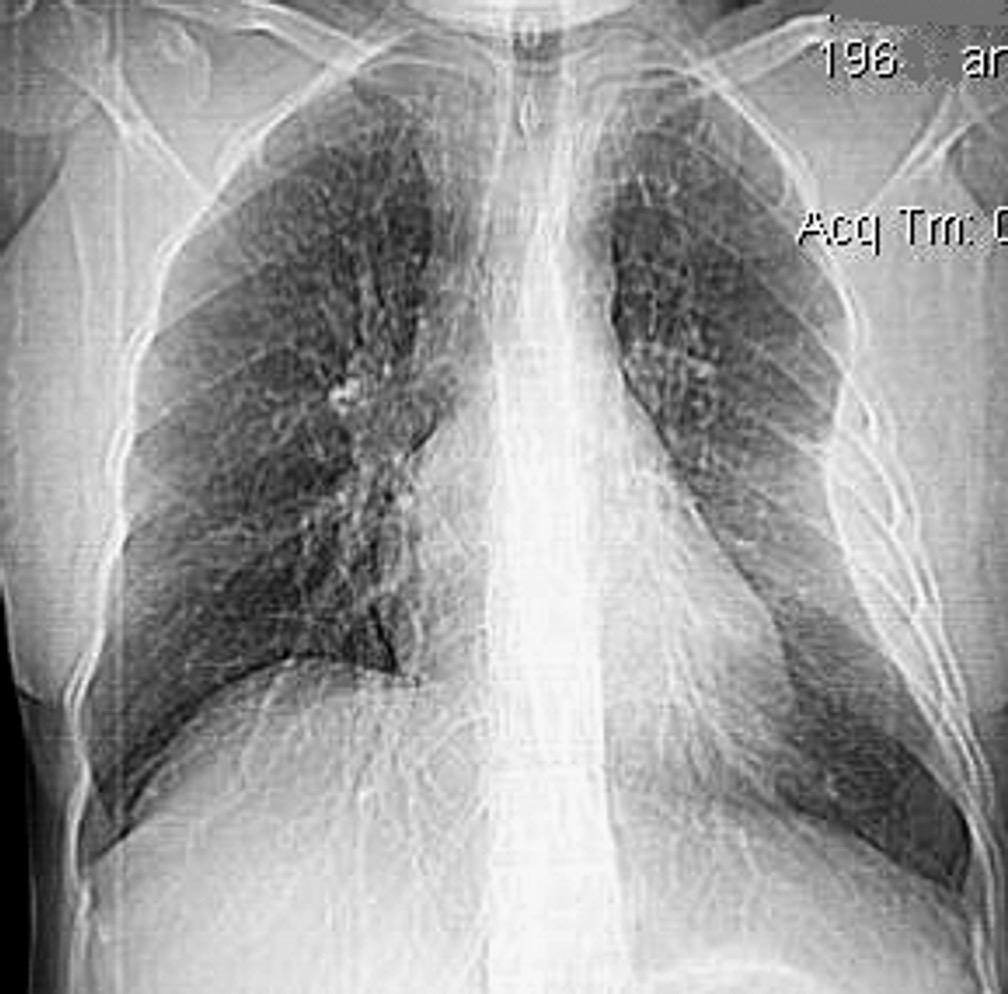

Rotura de aneurisma de arteria subclavia Aneurisma “deshinchado” Hemotórax

Fallece en el acto de tomar esta radiografía. La mayoría ateroescleróticos. Más frecuente a la derecha.La rotura: 32-47% de las muertes.

Sun J et al. Isolated True Subclavian Aneurysm without Aberrant Subclavian Artery or Coarctation of Descending Aorta. Annals of Vascular Surgery 2021

Johansson G, et al. Ruptured thoracic aortic aneurysms: a study of incidence and mortality rates. J Vasc. Surg. 1995;